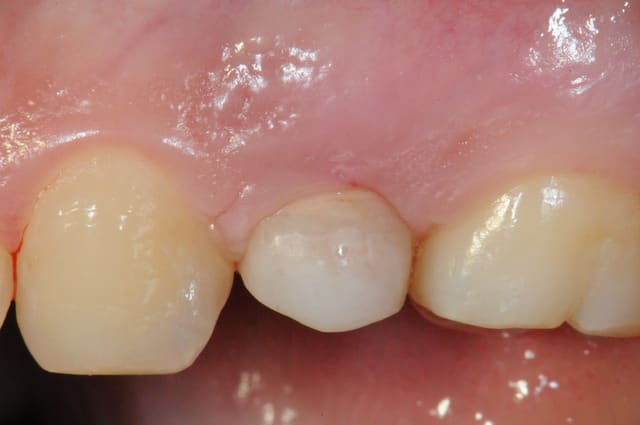

je rebondis sur ton titre" ne jamais faire de jolie provisoire", car ça me rappel une patiente.

25 ans, implanté en 2009

extraction-Summers-implantation- MCI sur une "jolie" provisoire avec du composite montée sur un pilier en pick...

(dernière photo contrôle à 15jours)

je l'ai rappelé il y a un an; pas de nouvelles, la provisoire doit lui convenir...

ps: c'est peu être le seule implant dont j'espère qu'il tombera. NA!

conclusion: ne jamais faire de jolie provisoire